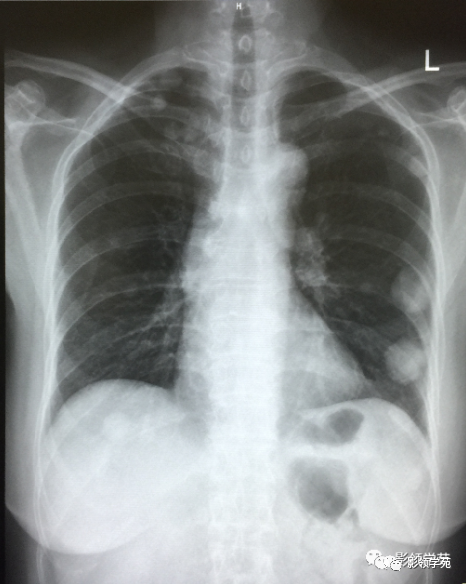

肿瘤外科患者,女55,9月前阴道不规则流血,诊刮术病检:子宫内膜浆液性腺癌(IV期),肺转移癌,盆腔淋巴结转移,骨转移,晚期无手术可能,省肿瘤TC方案化疗4周期,我院PAC方案化疗3疗程。

1. 血行性转移 :多发或单发结节,大小不一,边缘较清楚。少数结节伴出血时出现晕轮征,即有略高密度影像环绕结节,使病变边缘模糊。病变有钙化常见于骨肉瘤或软骨肉瘤转移。转移瘤亦可表现为空洞。两肺多发的小结节影具有随机分布的特点,HRCT显示结节位于小叶中心、小叶间隔、支气管血管束及胸膜,结节大小不均匀。

2.淋巴道转移:HRCT表现为沿淋巴管分布的结节。支气管血管束结节状增粗,并有结节,小叶间隔呈串珠状改变或增粗,小叶中心有结节灶,并有胸膜下结节。病变在两肺弥漫分布或局限于某一部位,以中下肺多见。常合并胸腔积液。约半数病人有纵隔及肺门淋巴结肿大。